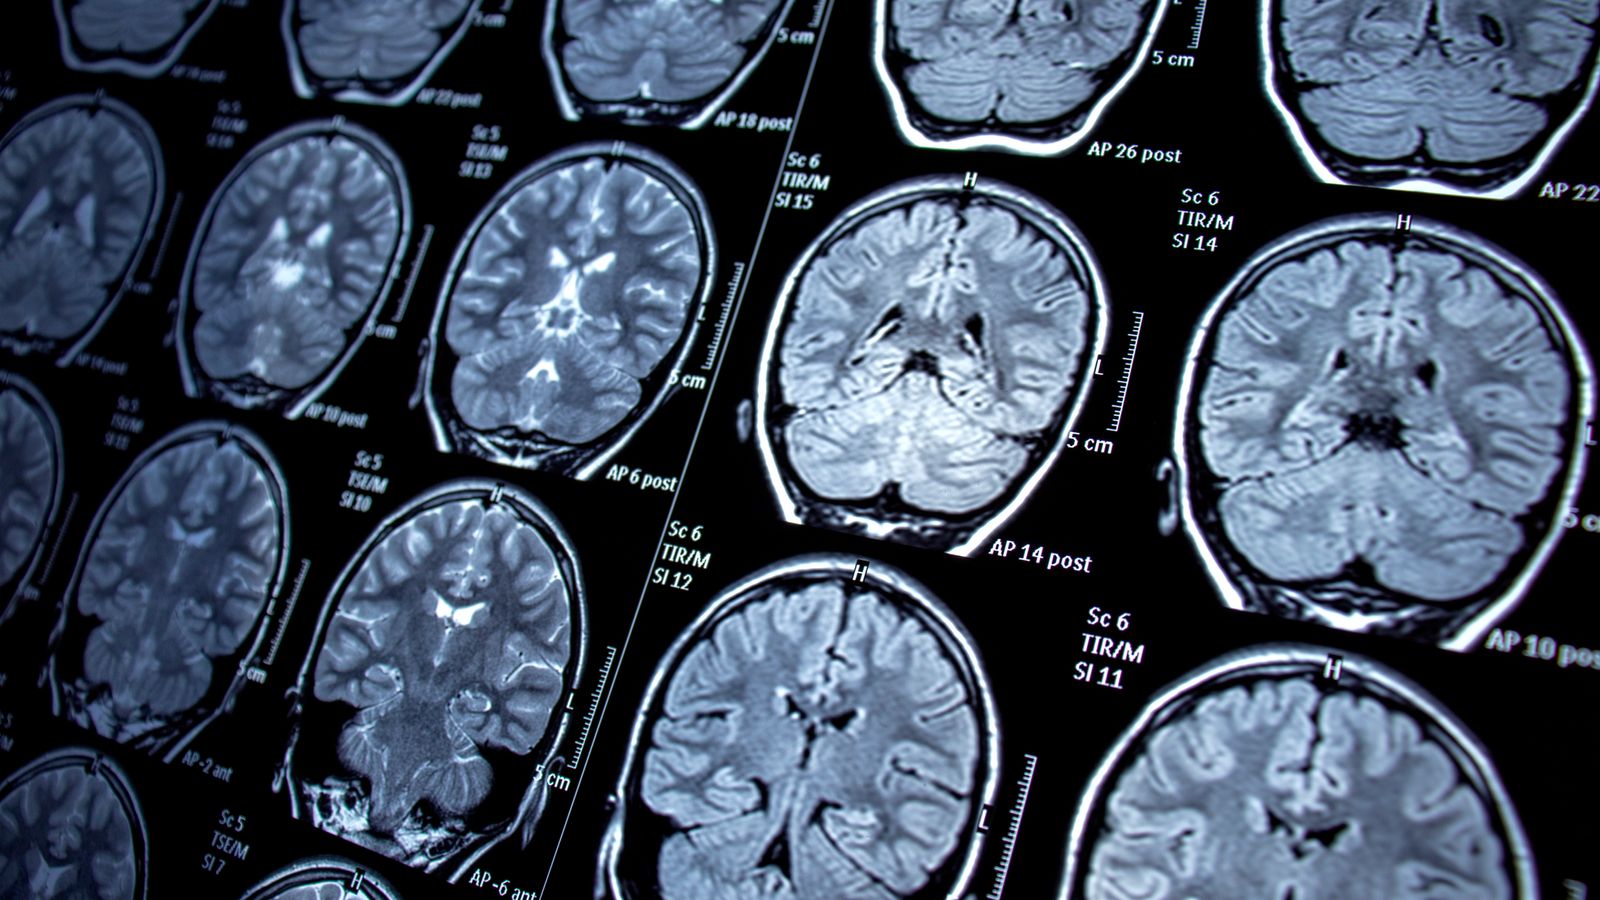

Brain fog suffered by those with long COVID could be caused by leaky blood vessels, new research shows.

Their findings, published in Nature Neuroscience, showed that those with long COVID who had leaks in the blood-brain barrier had brain fog, while those without disruption did not.

“For the first time,” he said, “we have been able to show that leaky blood vessels in the human brain, in tandem with a hyperactive immune system, may be the key drivers of brain fog associated with long COVID.

“It also confirms that the neurological symptoms of long COVID are measurable with real and demonstrable metabolic and vascular changes in the brain,” he added.

In their report, the team noted that “disruption is evident during acute infection and in patients with long COVID with cognitive impairment”, but said that it is unclear how “function is affected in these conditions”.